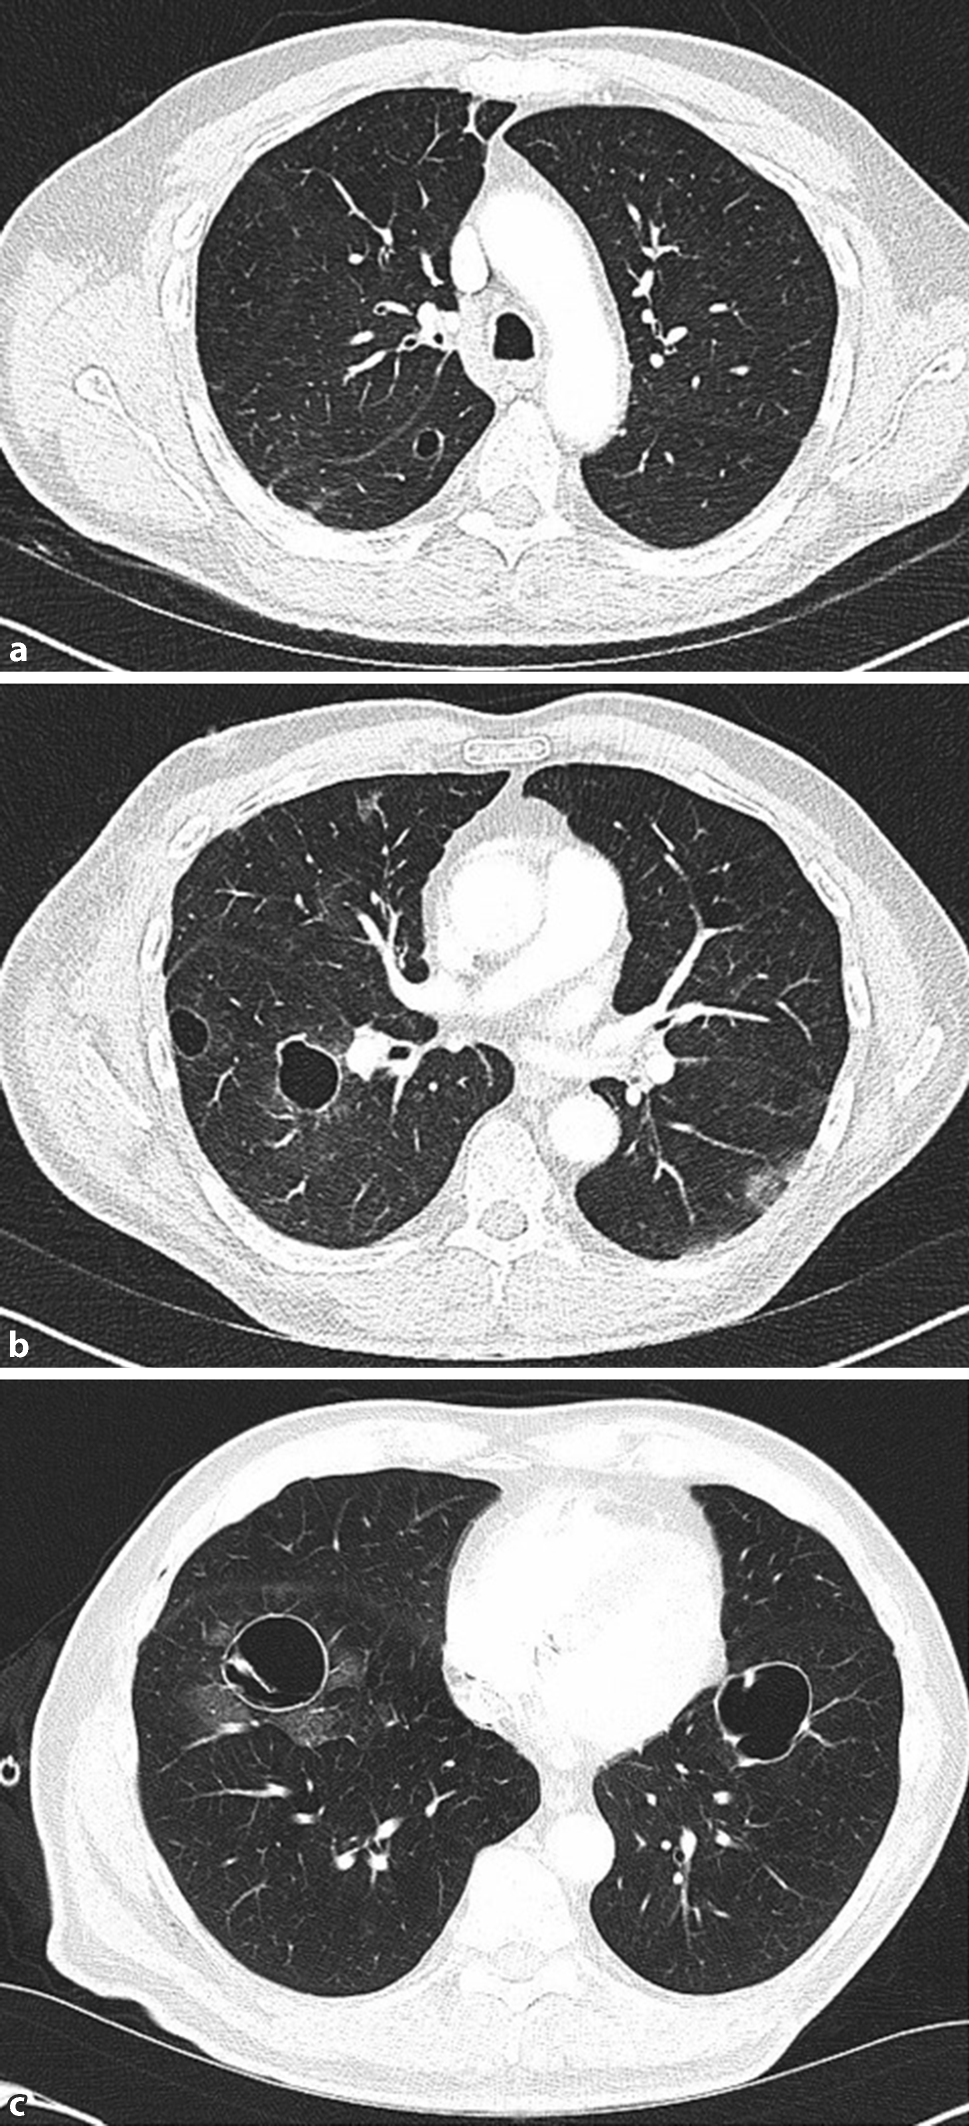

Thoracic CT scan again showed progression. The bilateral lesions had increased in maximum diameter by 3 to 6 mm each, and measured between 10 and 47 mm (Fig. 1). After chest-tube drainage the lung re-expanded; however, there was a pronounced pulmopleural fistula. During thoracoscopy, a ruptured cyst in the apical segment of the lower lobe was identified and removed by wedge resection.

Fig. 1

Thin-walled pulmonary cysts in the right and left lower lobes in the a upper, b middle, and c lower lung fields